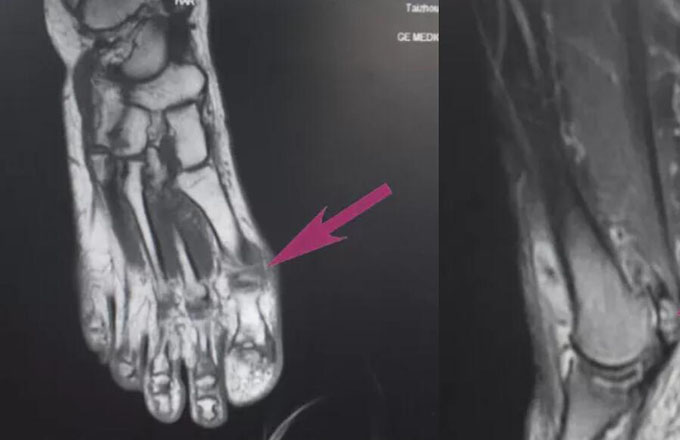

每天行走在刀尖上的“人鱼公主”,疼痛居然是因为脚上长出了一颗“心”!

本网讯(文化策划中心丁建萍/文)海的女儿人鱼公主为了和心爱的王子生活在一起,向巫婆讨了一锅汤,她喝了后就拥有了一条纤细笔直的腿,但是每走一步,都会像走在刀尖上一样,疼痛剧烈。 &emsp...2020-08-282002 -